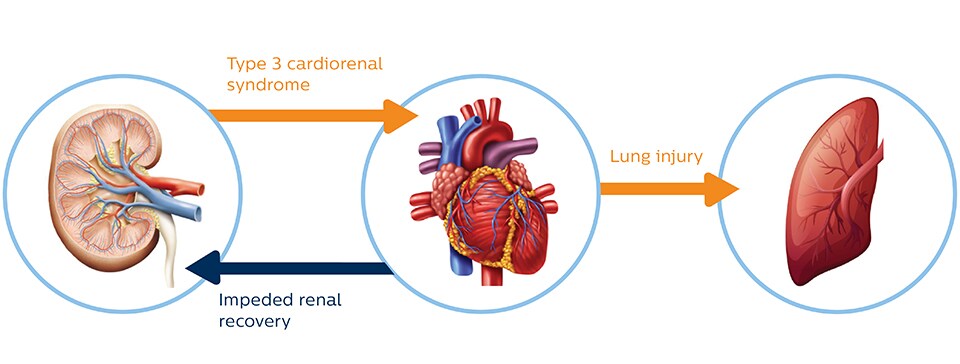

Cardiac and pulmonary consequence of AKI

AKI has been shown to promote cardiac injury and dysfunction, defined as type 3 cardiorenal syndrome. Heart failure, in turn, can impede renal recovery. Lung injury and hypoxemia after acute kidney injury can arise both from increased capillary permeability and from increased hydrostatic capillary pressure due to heart failure.6